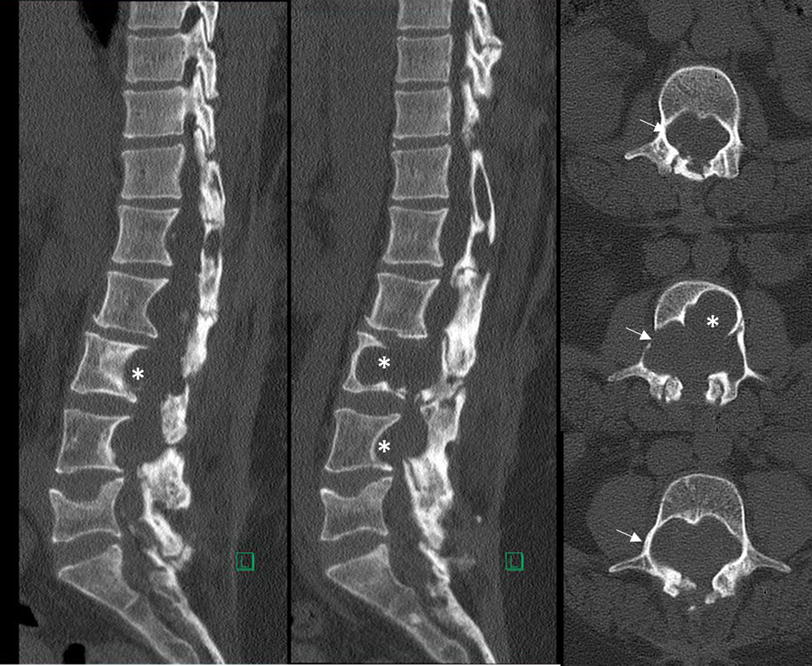

Severe erosion of lumbar vertebral body because of a chronic ruptured Erosion Of Spine When these disks wear out, people typically experience back. bone erosions, or simply, erosions, refer to focal bony defects in the subchondral bone plate or cortical bone and. It can also be spread from another place in your body to your. infection typically begins in the anterior metaphyseal region of the vertebral body and spreads to the disk. Erosion Of Spine.